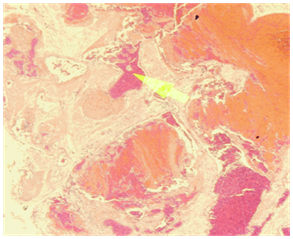

A 9 years old girl, presented with longstanding, left sided nasal obstruction and serosanguinous nasal discharge. She had been experiencing nasal obstruction and intermittent epistaxis for one year already. Her past medical history was otherwise unremarkable. The patient on anterior rhinoscopy, a bulge was detected, arising from the left nasal wall and impinging on the septum. The computed tomography (CT) examination was performed on a spiral scanner. The CT scan obtained following intravenous contrast administration revealed a large, inhomogeneously enhancing mass in the left maxillary sinus and nasal cavity (Figure 1–3). The nasal turbinates and the medial wall of the maxillary sinus had been eroded by the mass. There was also a bony remodeling in the anterior wall of the maxillary sinus. Because of the suspicion of sinonasal cancer, a biopsy was taken to obtain tissue from the nasal cavity and maxillary sinus. However, the biopsy revealed multiple submucosal dilated vessels filled with blood, fibrin deposition and organized thrombi stain for fungal organism negative, findings consistent with hemangioma. The microscopic examination showed dilated sinusoidal vascular channels in the stroma lining with an interconnecting fibrous wall covered with flat endothelium. The Lumina of these spaces were filled with blood. The histologic features were most compatible with cavernous hemangioma (Figure 4). On follow up, patient improvement regarding nasal obstruction and less nasal bleeding.

Figure 4 Multiple sub mucosal dilated vessels filled with blood, fibrin deposition and organized thrombi. Stain for fungal organism is negative. Findings consistent with Hemangioma “Cavernous Hemangioma”